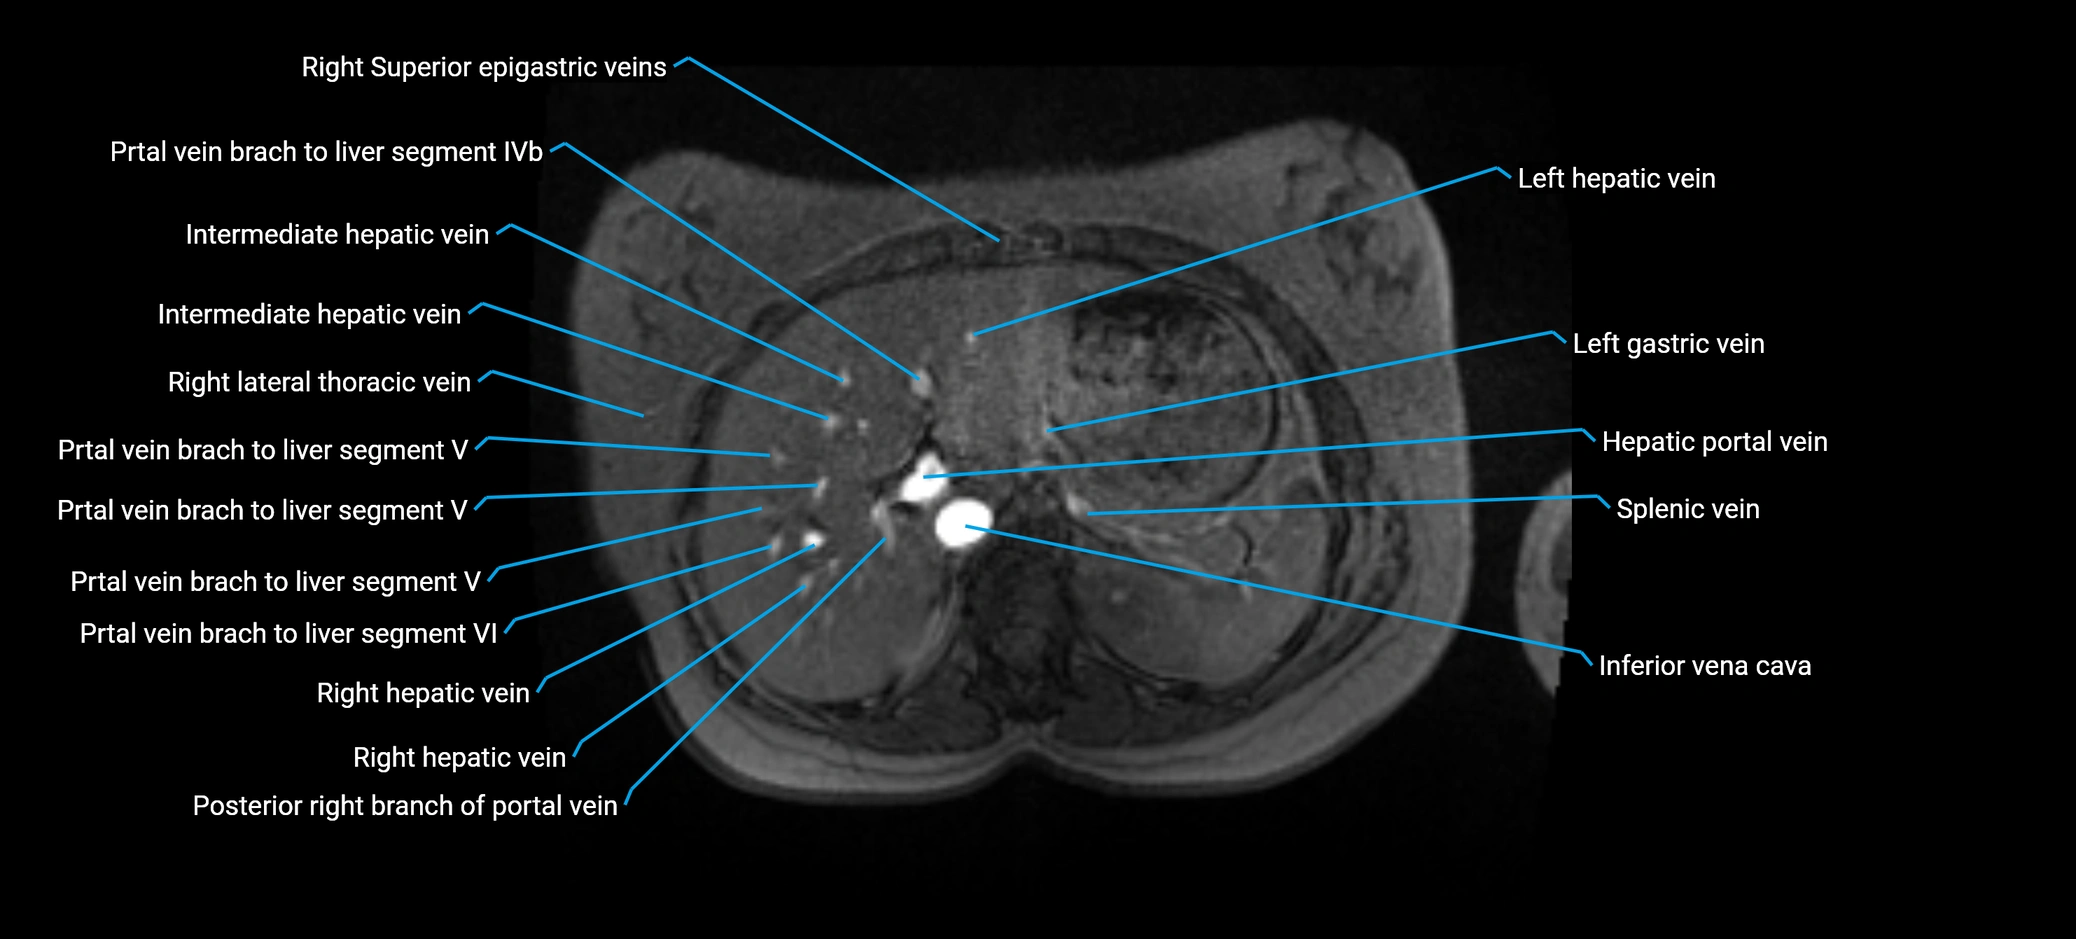

MRI image

image